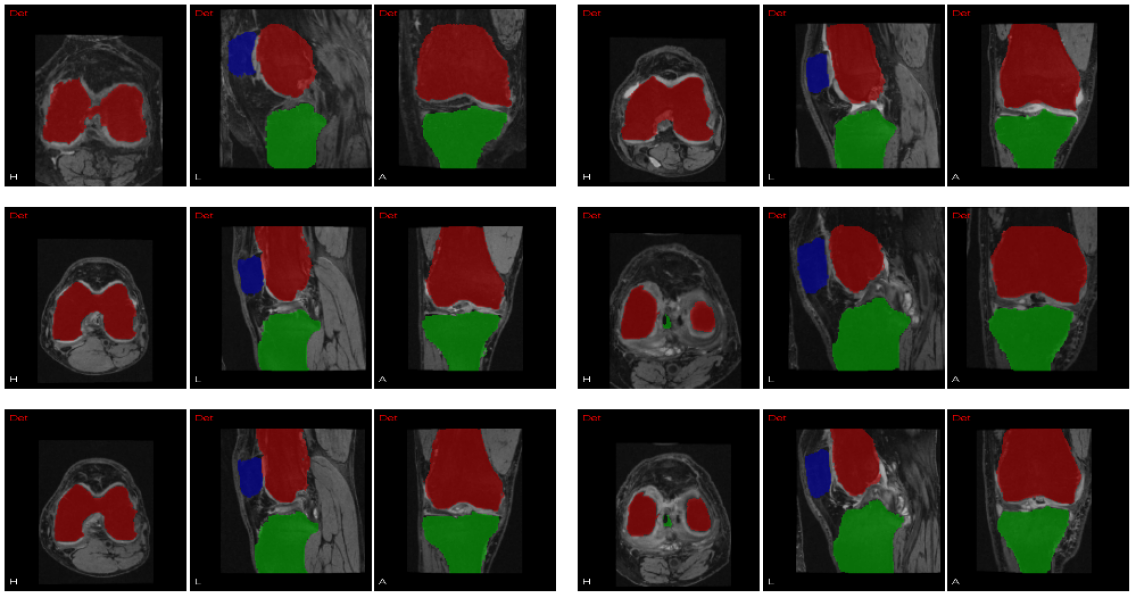

Finally, the quantitative results (2-pass classification) are listed in Table 2 together with the numbers reported in the earlier literature. Because the datasets used are different by all these approaches, the numbers in the table are only for reference. Note that only our experiments are based on a relatively large dataset. As shown in the table, we achieved high performance with regard to the femoral and tibial cartilage, whereas the DSC of patellar cartilage is notably lower than the other two cartilages. This is partly because the size of patellar cartilage is much smaller than femoral and tibial cartilage, so that the same amount of segmentation error will result in lower DSC. Besides, some patellar cartilage annotations in the dataset do not appear very consistent with others. Example segmentation results are shown in Fig. 5.

Figure 4: Example bone segmentations. Each case has three views, from left to right: transversal plane, sagittal plane, coronal plane. Red: femur; green: tibia; blue: patella.

Figure 5: Examples cartilage segmentations compared with ground truth. Each case has six images: segmentation results in upper row, ground truth in lower row. Red: femoral cartilage; green: tibial cartilage; blue: patellar cartilage.